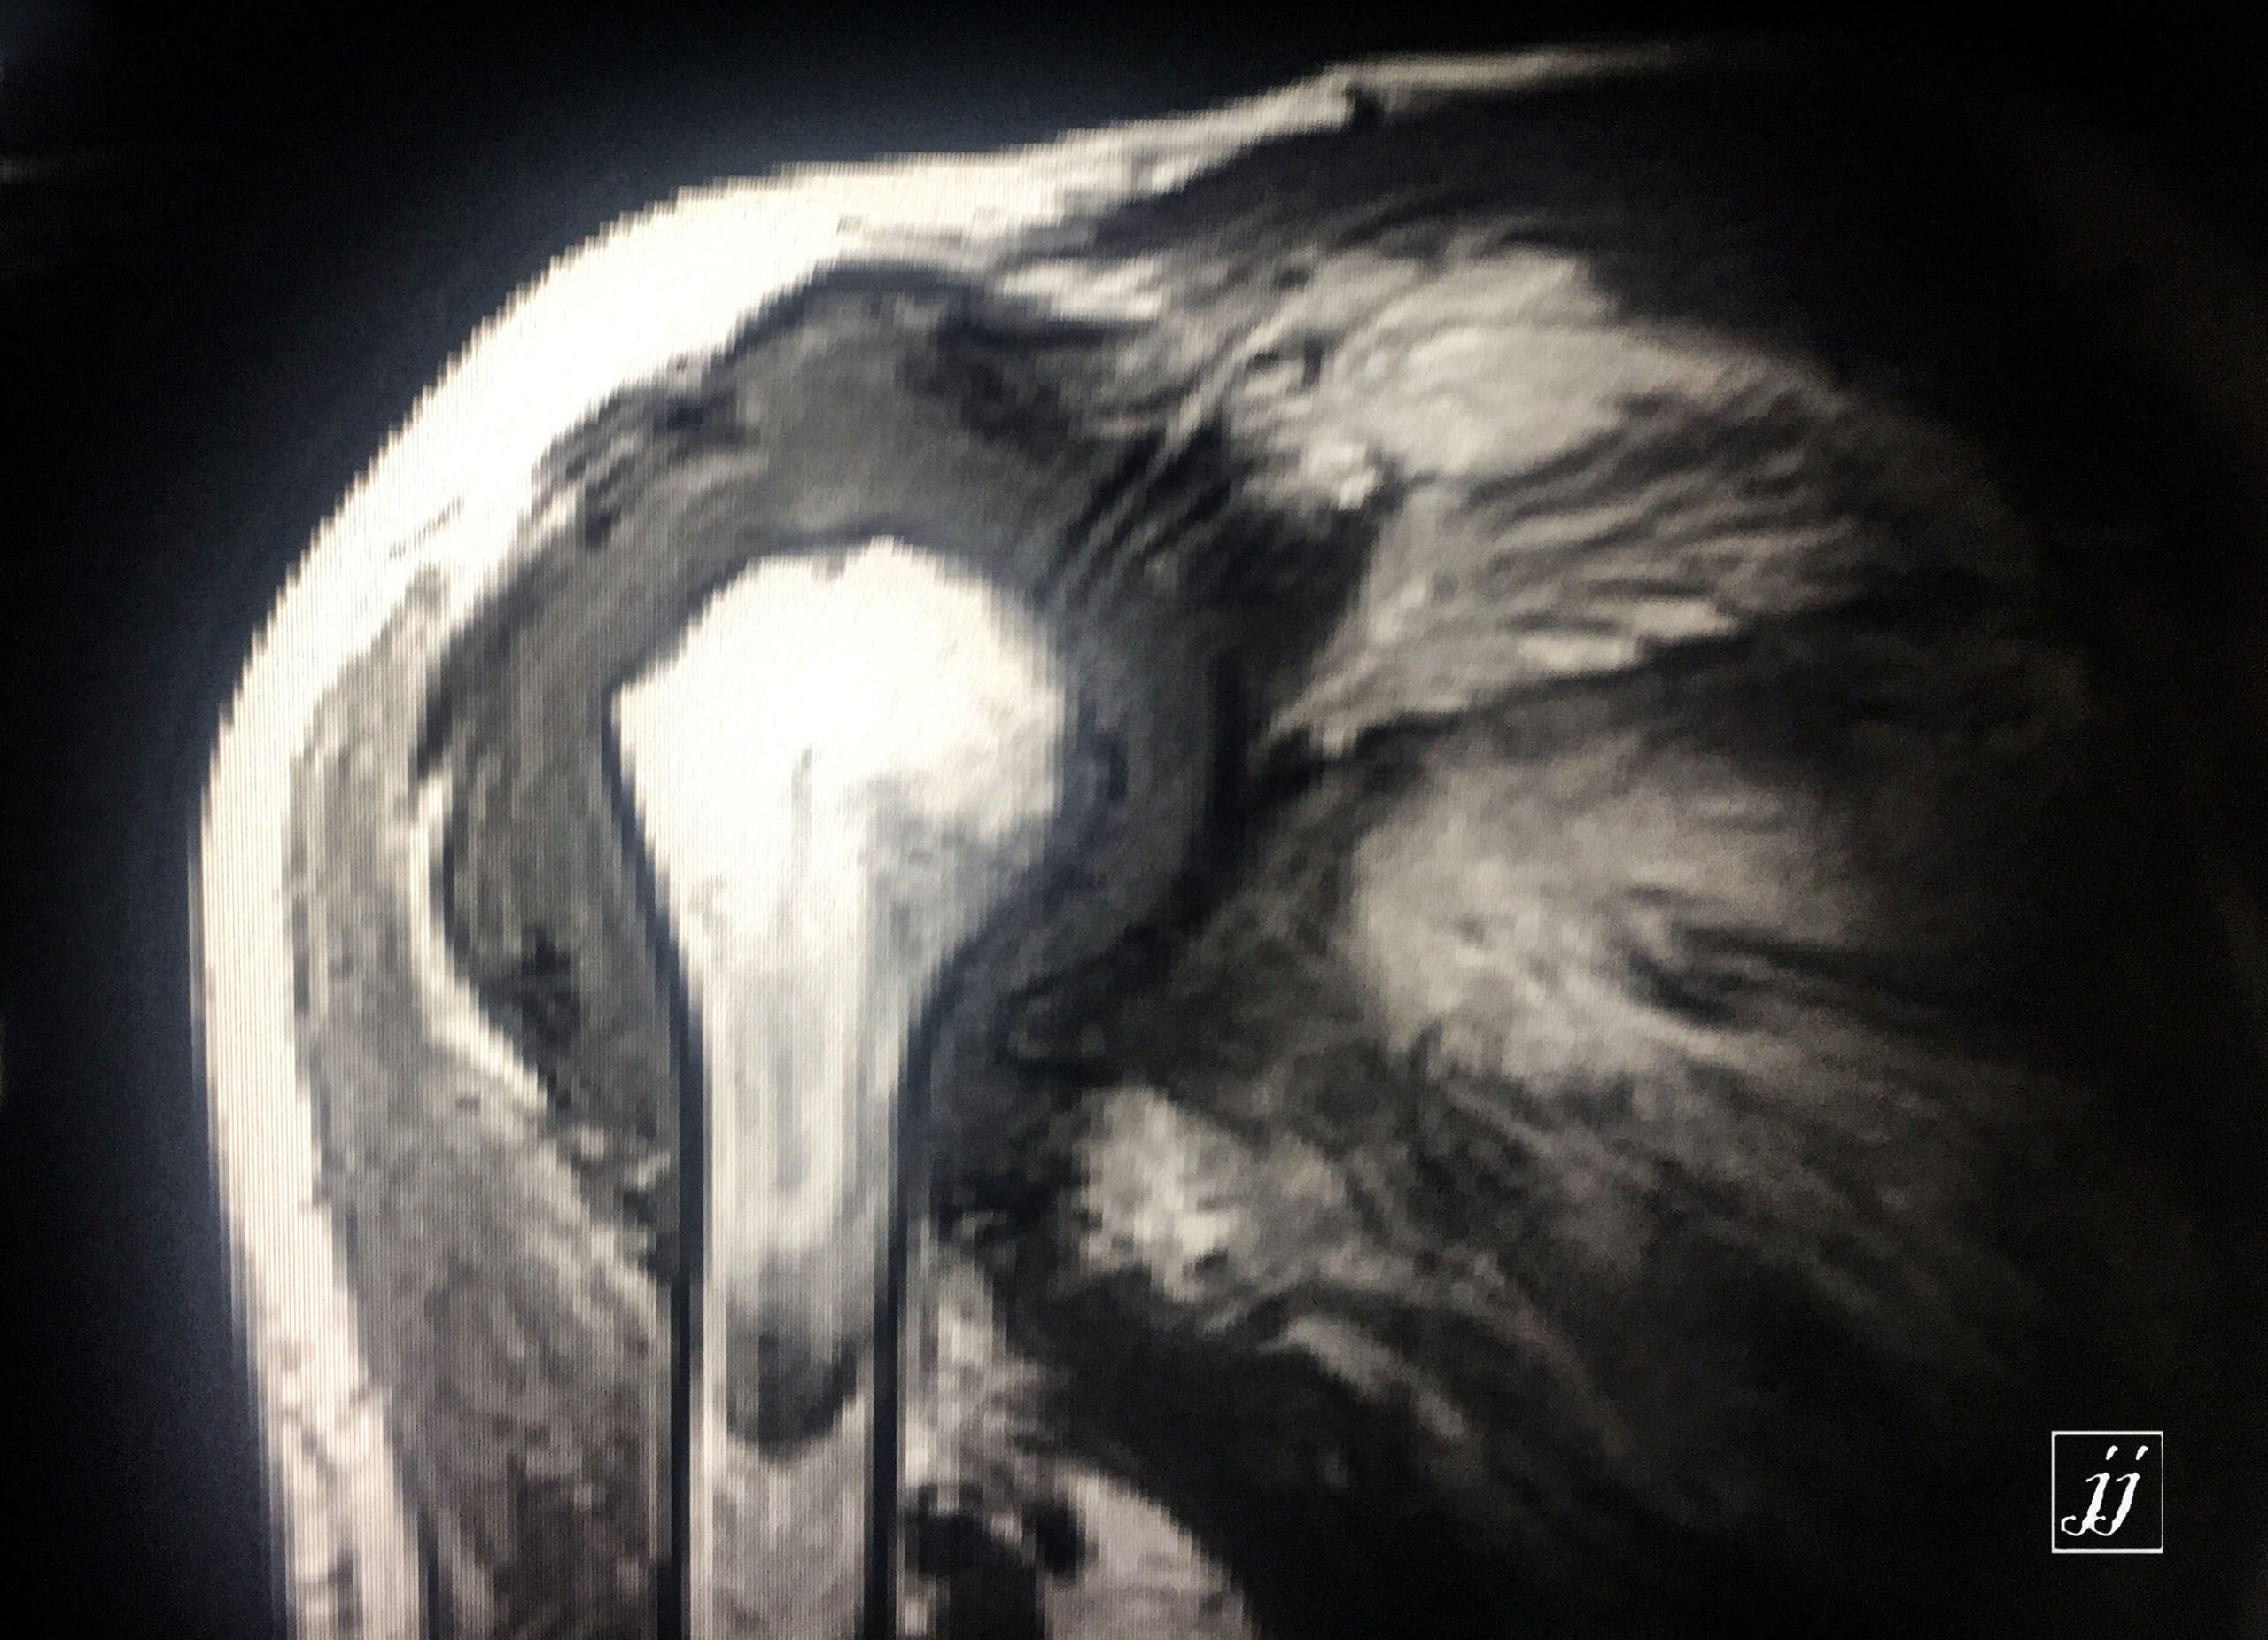

MSK- hugged size shoulder joint arthritis effusion, RA (6)